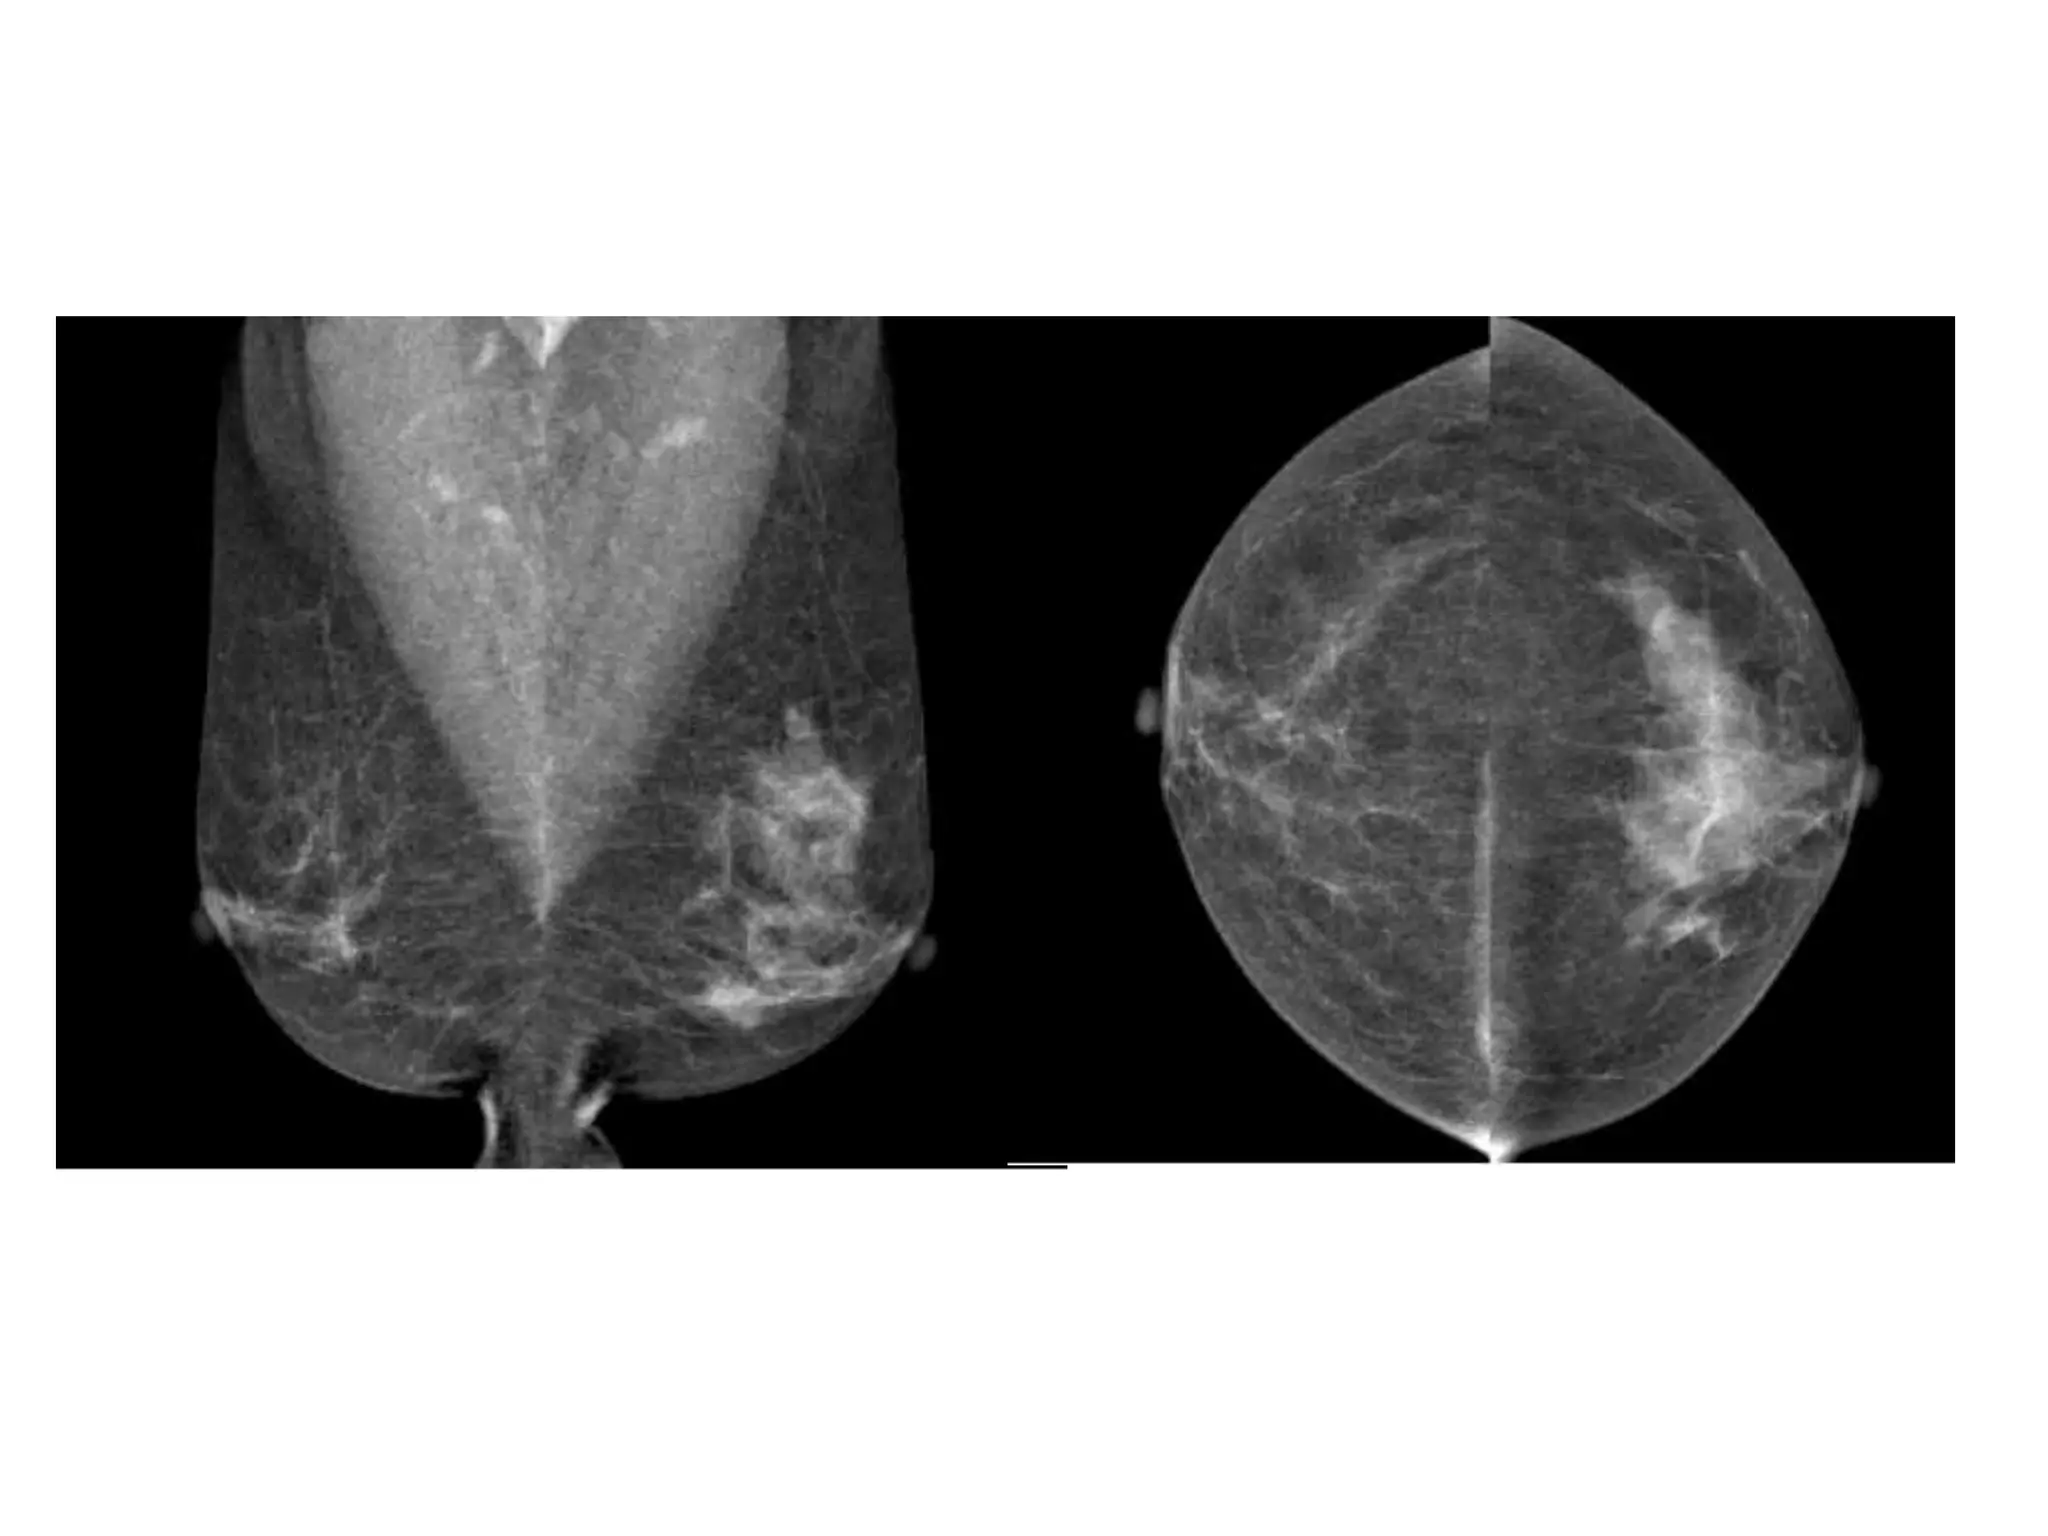

BI-RADS BREAST COMPOSITION

• The American College of Radiology Breast

Imaging and Reporting Database System (BIRADS)divides breast composition into four

categories:

• 1) almost entirely fat,

• 2) scattered fibroglandular densities

(approximately 25-50% glandular),

• 3) heterogeneously dense (51-75% glandular),

• 4) extremely dense (greater than 75% glandular).